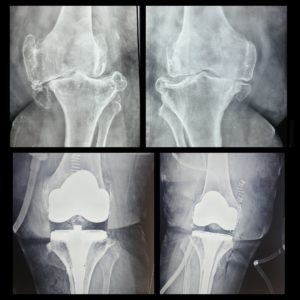

History: 70-yr-old female unable to walk because of severe varus deformity with multiple big osteophytes.

Case:  A single-stage Bilateral Total Knee Replacement was performed with long stem. Long stem is better to use in obese patient with osteoporosis with severe deformities, it avoids periprosthetic fractures and adds more stability to the construct.